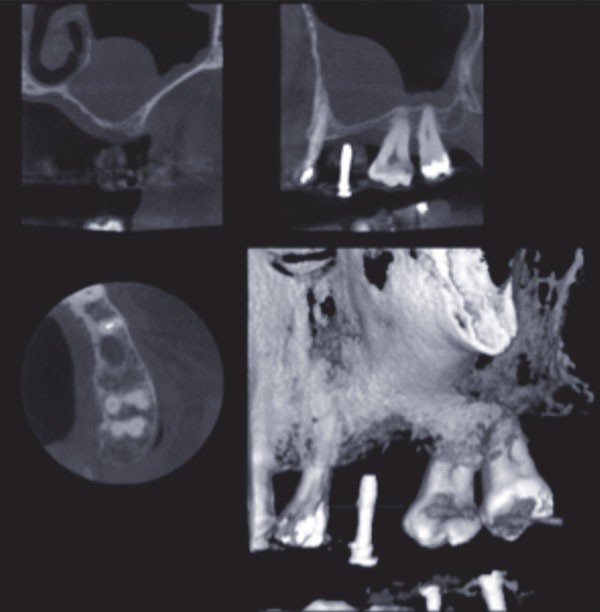

La largeur de la crête sera alors estimée mais seule l’analyse d’un cliché radiographique en 3D de type Cone Beam (CBCT) sera à même de préciser le volume osseux disponible. En cas d’insuffisance, de volume osseux vertical une élévation de sinus pourra être proposée (fig. 2).